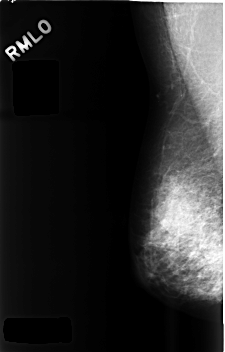

C_0481_1.RIGHT_MLO

RIGHT_MLO LINES 4576 PIXELS_PER_LINE 2920 BITS_PER_PIXEL 12 RESOLUTION 50 NON_OVERLAY